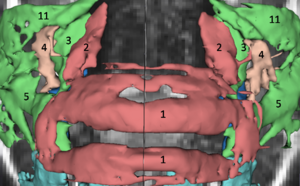

Boolean Combinations of Implicit Functions for Model Clipping in Computer-Assisted Surgical Planning

Publication: PLoS One. 2016 Jan 11;11(1):e0145987. PMID: 26751685 | PDF Authors: Zhan Q, Chen X. Institution: School of Mechanical Engineering, Shanghai Jiao Tong University, Shanghai, China. Background/Purpose: This paper proposes an interactive method of model clipping for computer-assisted surgical planning. The model is separated by a data filter that is defined by the implicit function of the clipping path. Being interactive to surgeons, the clipping path that is composed of the plane widgets can be manually repositioned along the desirable presurgical path, which means that surgeons can produce any accurate shape of the clipped model. The implicit function is acquired through a recursive algorithm based on the Boolean combinations (including Boolean union and Boolean intersection) of a series of plane widgets' implicit functions. The algorithm is evaluated as highly efficient because the best time performance of the algorithm is linear, which applies to most of the cases in the computer-assisted surgical planning. Based on the above stated algorithm, a user-friendly module named SmartModelClip is developed on the basis of Slicer platform and VTK. A number of arbitrary clipping paths have been tested. Experimental results of presurgical planning for three types of Le Fort fractures and for tumor removal demonstrate the high reliability and efficiency of our recursive algorithm and robustness of the module. Funding:

|

A snapshot of the module SmartModelClip in 3D Slicer. On the left is the operator command view that users can create and manipulate clipping path and thickness plane(i.e., they can create, hide and delete plane widgets). Users can also reverse the directions of the axes of the both clipping path and thickness plane widget. On the right is the scene that users can interact with the clipping path. They can specify the fiducial points that position the clipping path and modify the boundary of the clipping path by dragging the handles to obtain the desirable clipping path. |